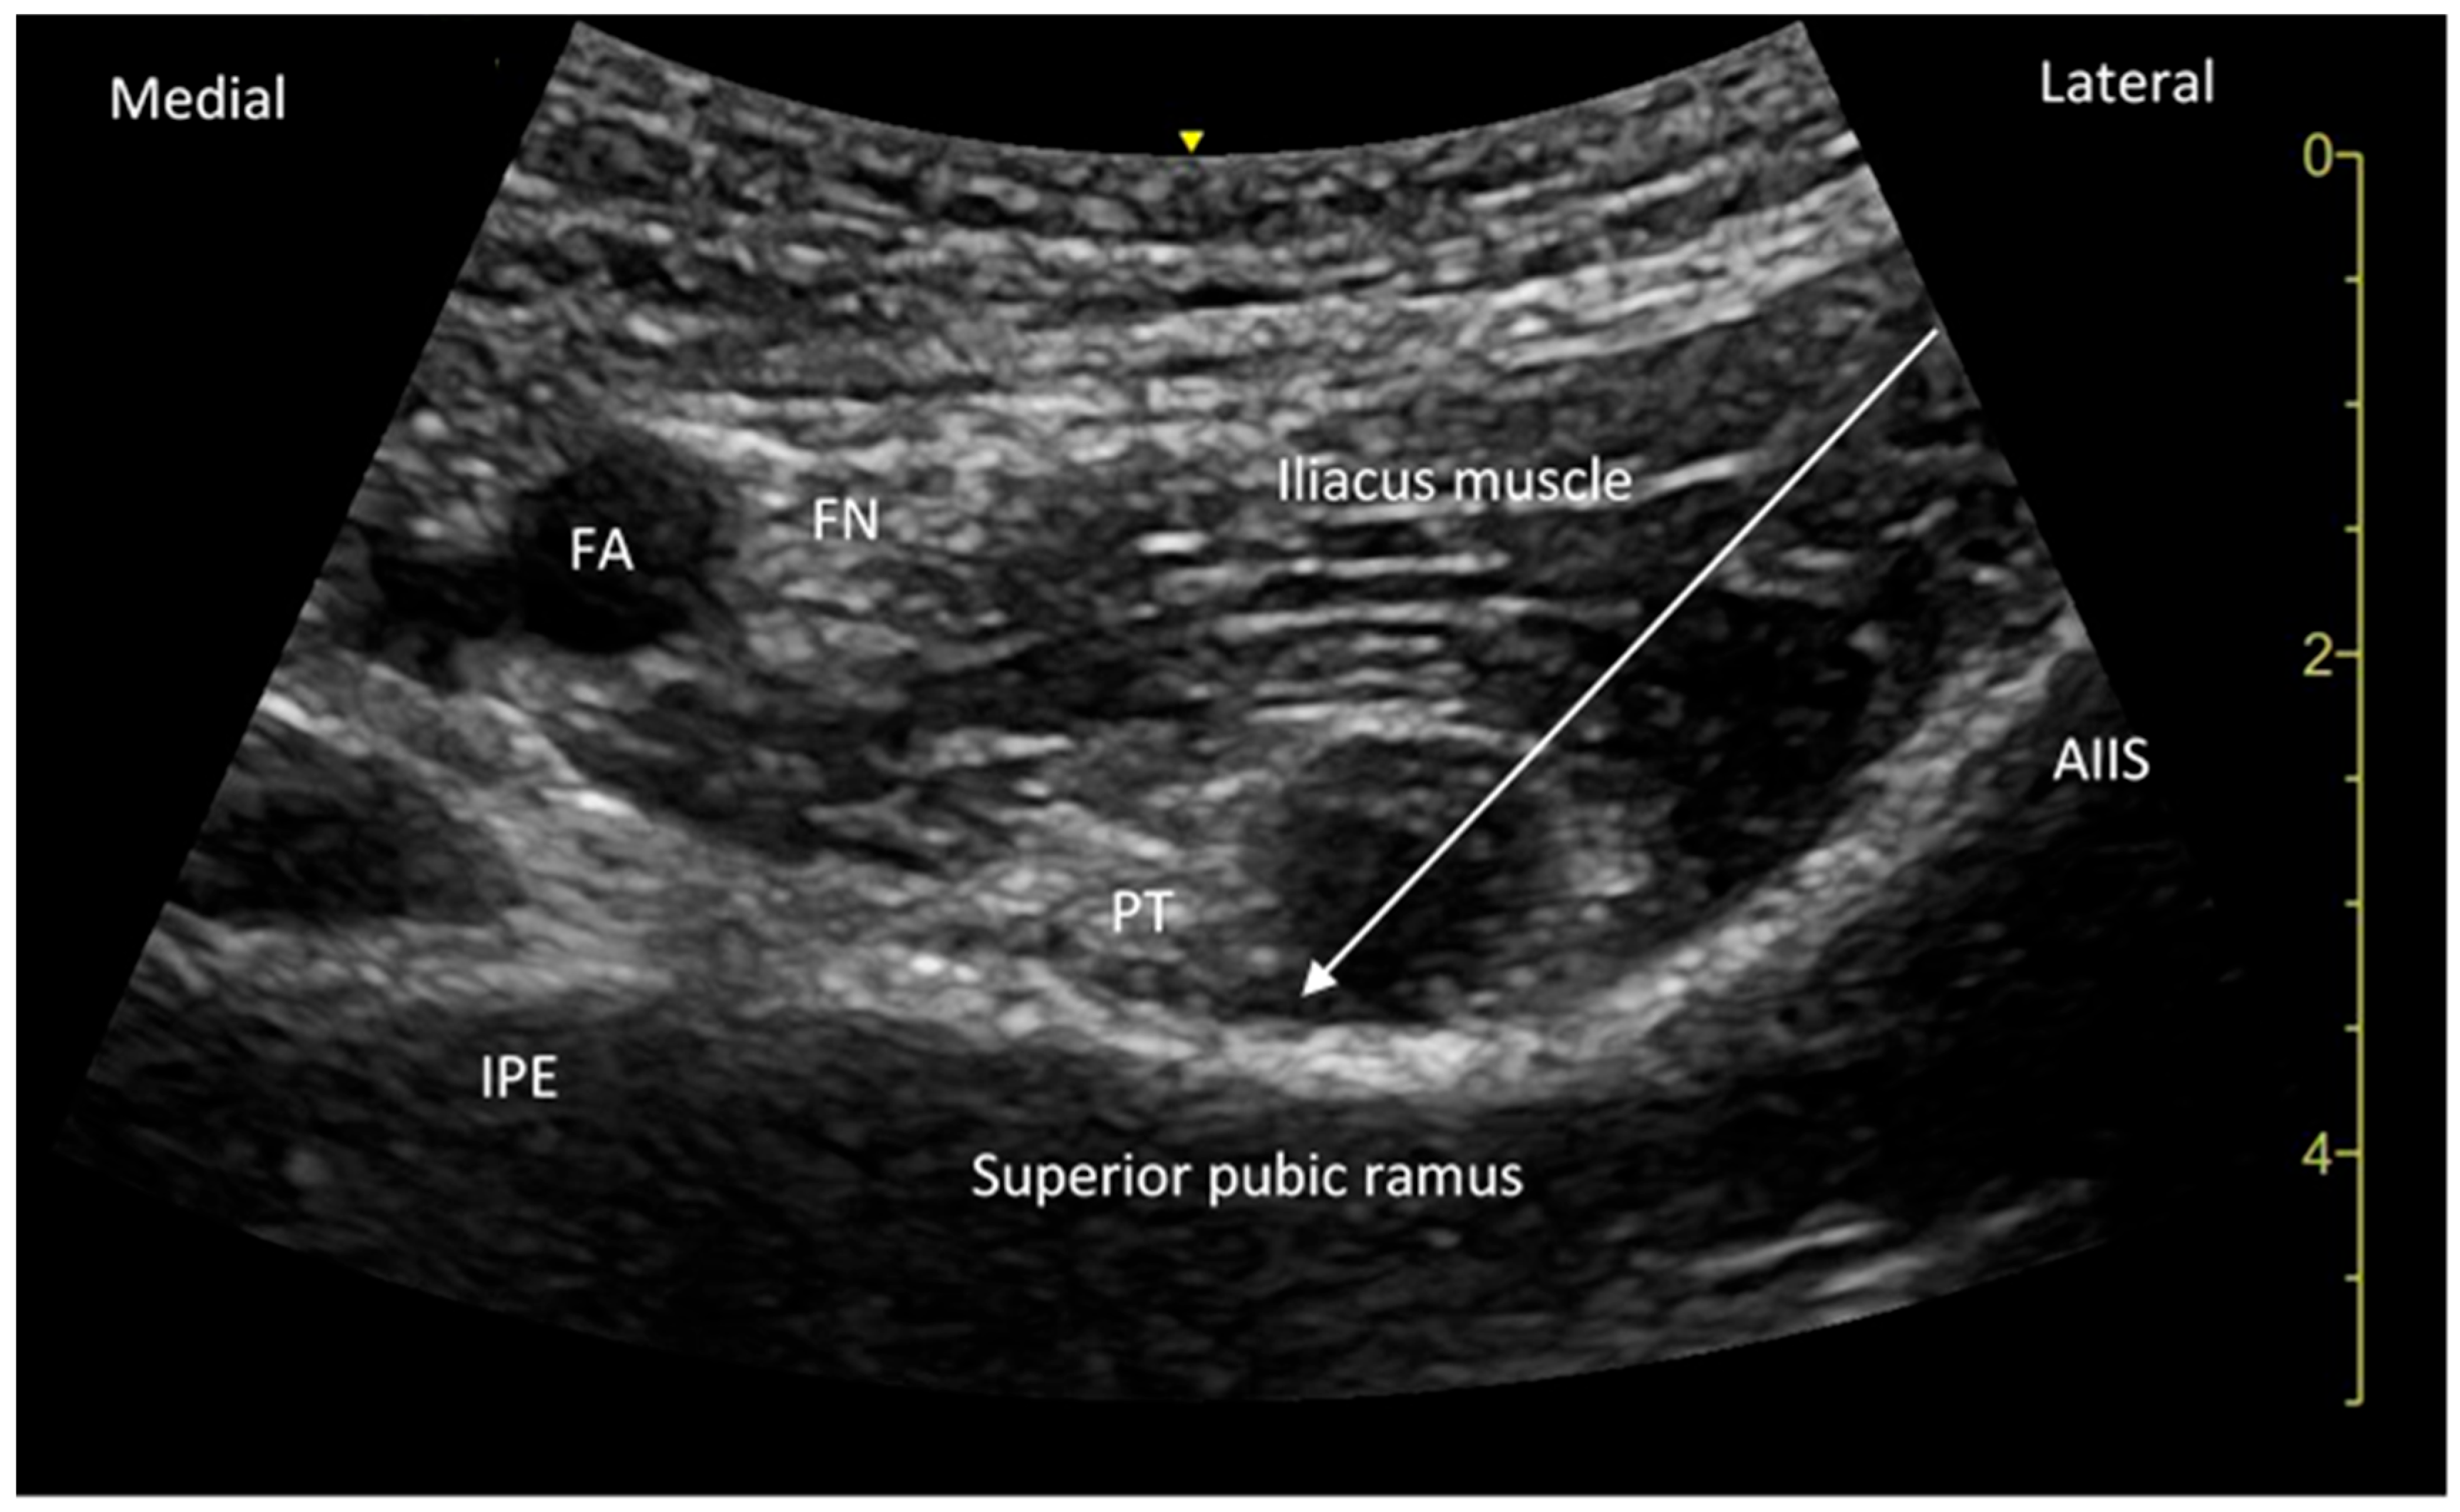

| AIIS | Anterior inferior iliac spine |

| IPE | Iliopubic eminence |